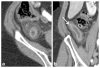

The appendix may demonstrate a perplexing range of normal and abnormal appearances on imaging exams. Familiarity with the anatomy and anatomical variants of the appendix is helpful in identifying the appendix on ultrasound, computed tomography, and magnetic resonance imaging. Knowledge of the variety of pathologies afflicting the appendix and of the spectrum of imaging findings may be particularly useful to the emergency radiologist for accurate diagnosis and appropriate guidance regarding clinical and surgical management. In this pictorial essay, we review appendiceal embryology, anatomical variants such as Amyand hernias, and pathologies from appendicitis to carcinoid, mucinous, and nonmucinous epithelial neoplasms.